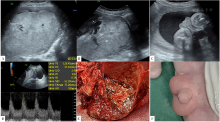

图4 病例5孕22<sup>+5</sup>周胎盘灌注不良

注:A为胎盘增厚,厚达6.0 cm,胎盘回声弥漫不均,探头晃动时其内见细点状回声蠕动,胎盘实质明显减少;B为彩色多普勒显示类血池样回声内未见血流分布,胎盘实质内血流分布明显减少